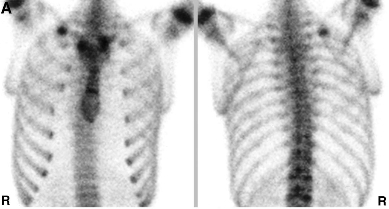

진단은 물론 X-ray 나 CT, bone scan 같은 영상검사로 하게 되지만

외상의 골절과는 다르게 여러개의 뼈가 부러지는 형태가 아닌 단일뼈가 부러지는 형태의

피로골절 형태의 골절이 생기는 경우가 많습니다.